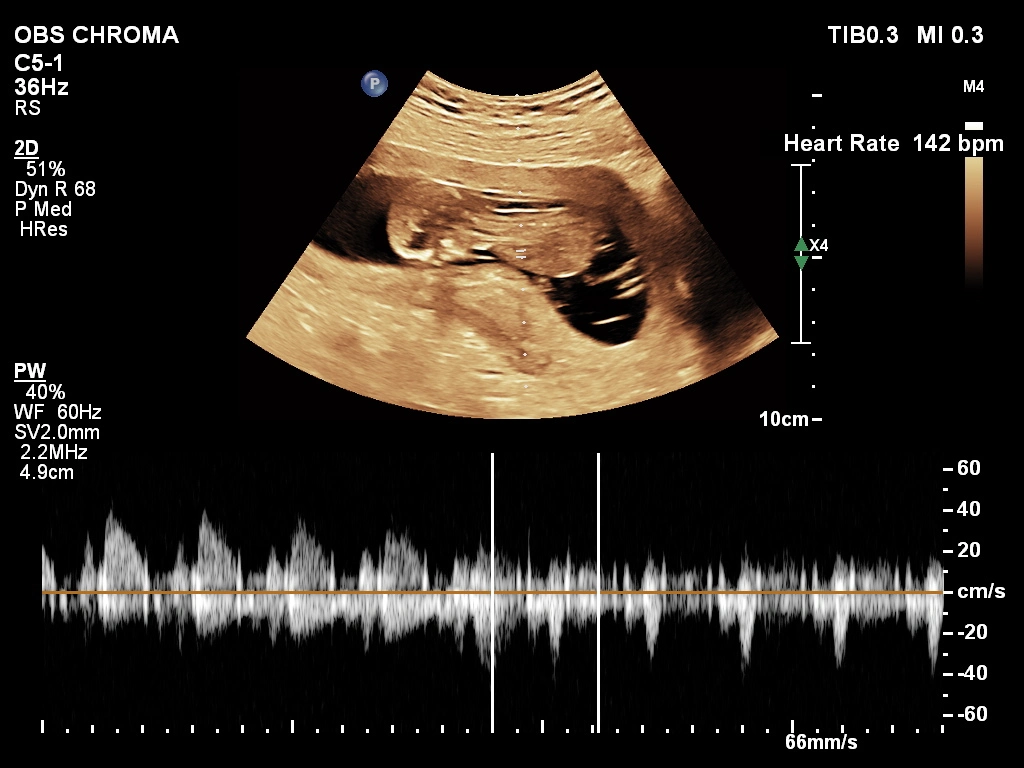

An NT/NB scan in Kathmandu (Nuchal Translucency and Nasal Bone ultrasound) is a specialized first-trimester test performed between 11 and 13 weeks of pregnancy. It measures the fluid at the back of the baby’s neck and evaluates the nasal bone. Additionally, this scan helps screen for chromosomal conditions such as Down syndrome.

This non-invasive ultrasound allows doctors to assess early pregnancy risks. Importantly, early detection supports better medical planning and follow-up care. At Lomash Health Care Center (Thapathali), our experienced team uses modern ultrasound technology to deliver accurate results on the same day.

First, the sonographer applies gel to your abdomen. Then, a handheld ultrasound device captures clear images of your baby. You can see your baby’s profile and neck area during the scan.